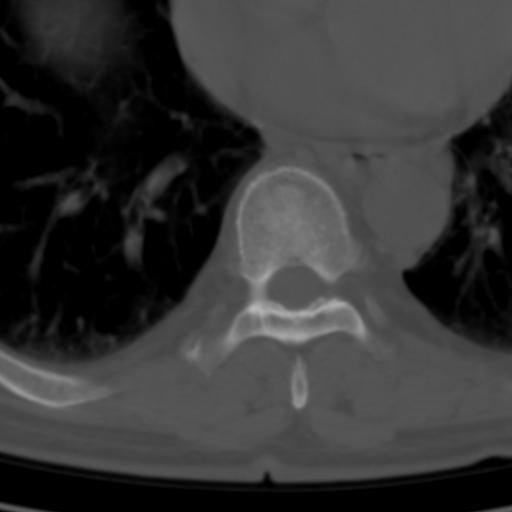

标题: CT25189:胸椎ct,请会诊! [打印本页]

标题: CT25189:胸椎ct,请会诊!

既往食管癌,现行ct检查!

仅见椎体退行性改变

中上段食道癌,椎体轻度退变。

椎体退行性改变,食管癌。

支持中上段食道癌,椎体轻度退变,必要时做ect。

支持中上段食道癌,椎体轻度退变。